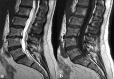

Low back pain is one of the most prevalent musculoskeletal ailments in the United States. Intraosseous radiofrequency ablation of the basivertebral nerve is an effective and durable therapy for low back pain and can be offered to patients who have chronic low back pain of greater than 6 months of duration, failure to respond to noninvasive therapies for 6 months, with either Modic Type I or Type II changes at L3-S1. This article reviews the anatomy and physiology, patient selection, technique, and evidence regarding basivertebral nerve ablation.